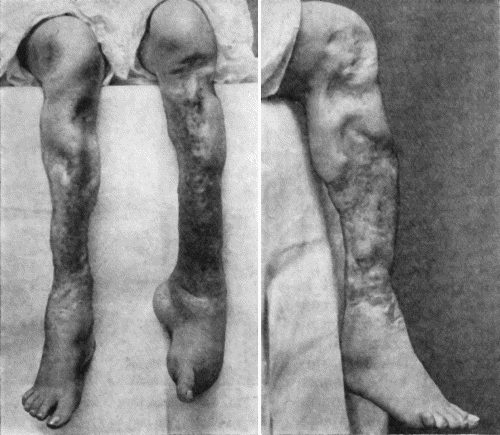

| 14. | Leg Ulcers associated with Varicose Veins | 71 |

| 67. | Extensive Varix of Internal Saphena System on Left Leg | 291 |